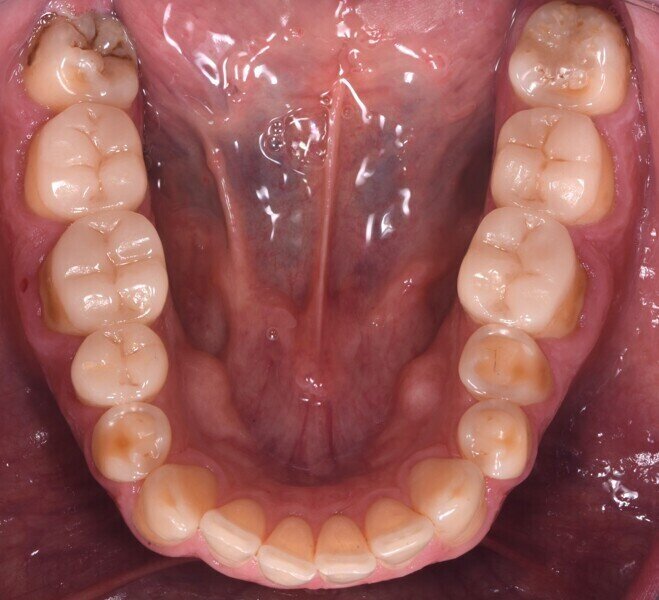

Do naší ordinace přišel 42letý muž, který doufal ve vylepšení svého úsměvu. Byl si vědom opotřebení chrupu v předním úseku a také některých zadních zubů. Tato situace vedla k obnažení značné oblasti dentinu, což způsobilo vysokou citlivost a negativně ovlivnilo estetiku jeho úsměvu (obr. 1). Dále se u něj projevilo určité stěsnání a vztah stoliček III. třídy, což mělo za následek určitou modifikaci okluze, tendenci ke vztahu řezáků III. třídy a skus hrana na hranu (obr. 2).

Pacient podstoupil částečnou rekonstrukci na jiné klinice před dvěma až třemi lety, ale ošetření molárů dolní čelisti, pravého druhého premoláru dolní čelisti a levého prvního premoláru horní čelisti zůstalo nedokončeno. Požadavkem pacienta bylo zachovat již provedené výplně, pokud jsou stále v dobrém stavu.